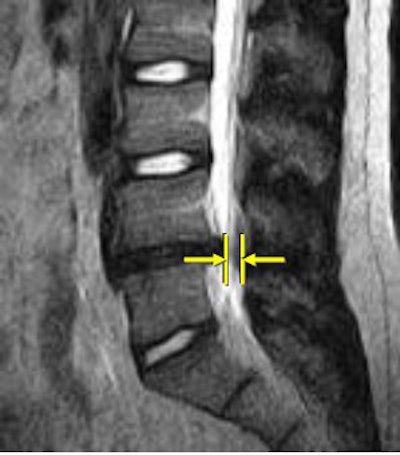

![]() |

| Above, nonaxial-loaded images. Below, axial-loaded images. Increase in stenosis at L4 level by 2.0 mm and left L4 spinal nerve root with axial loading. All images courtesy of Dr. Gerald Anzalone. |